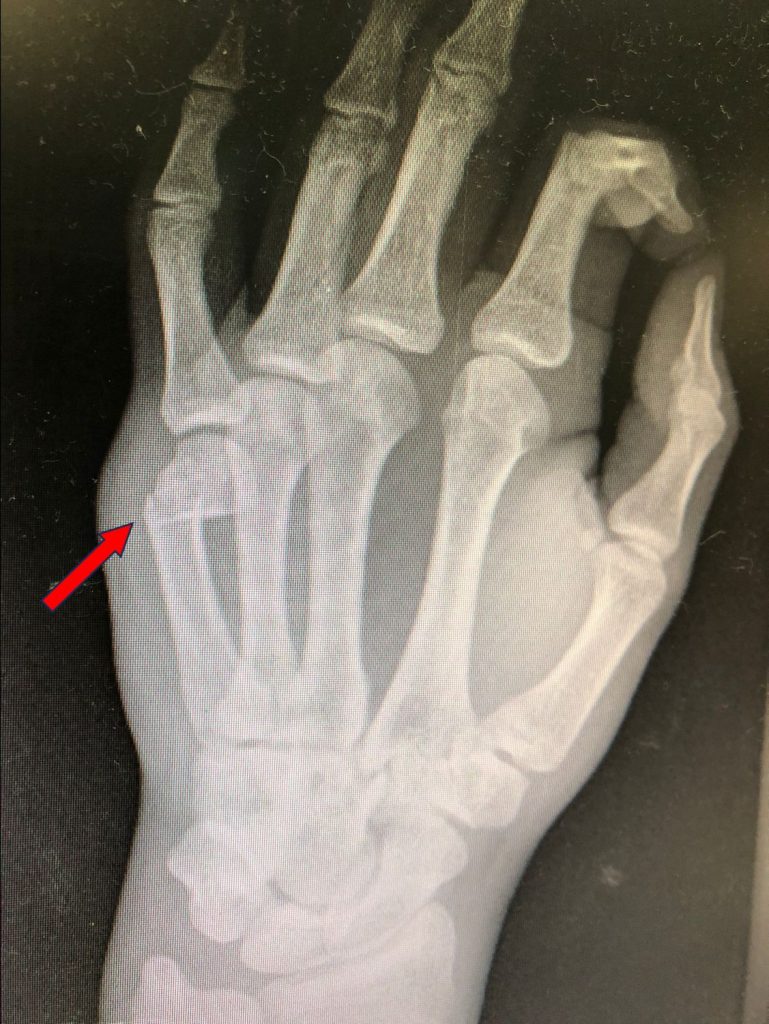

Fracturas de metacarpianos: (Figura 3) Muy habituales, especialmente las fracturas del boxeador, que afectan al cuello del quinto metacarpiano (Figura 4). Aparecen tras golpes con el puño mal cerrado y pueden necesitar inmovilización con férula, aunque algunas se tratan quirúrgicamente si hay desplazamiento. También se lesionan los otros metacarpianos por impactos repetidos o directos. Las fracturas desplazadas pueden requerir osteosíntesis.

Figura 4 - Fractura del boxeador.